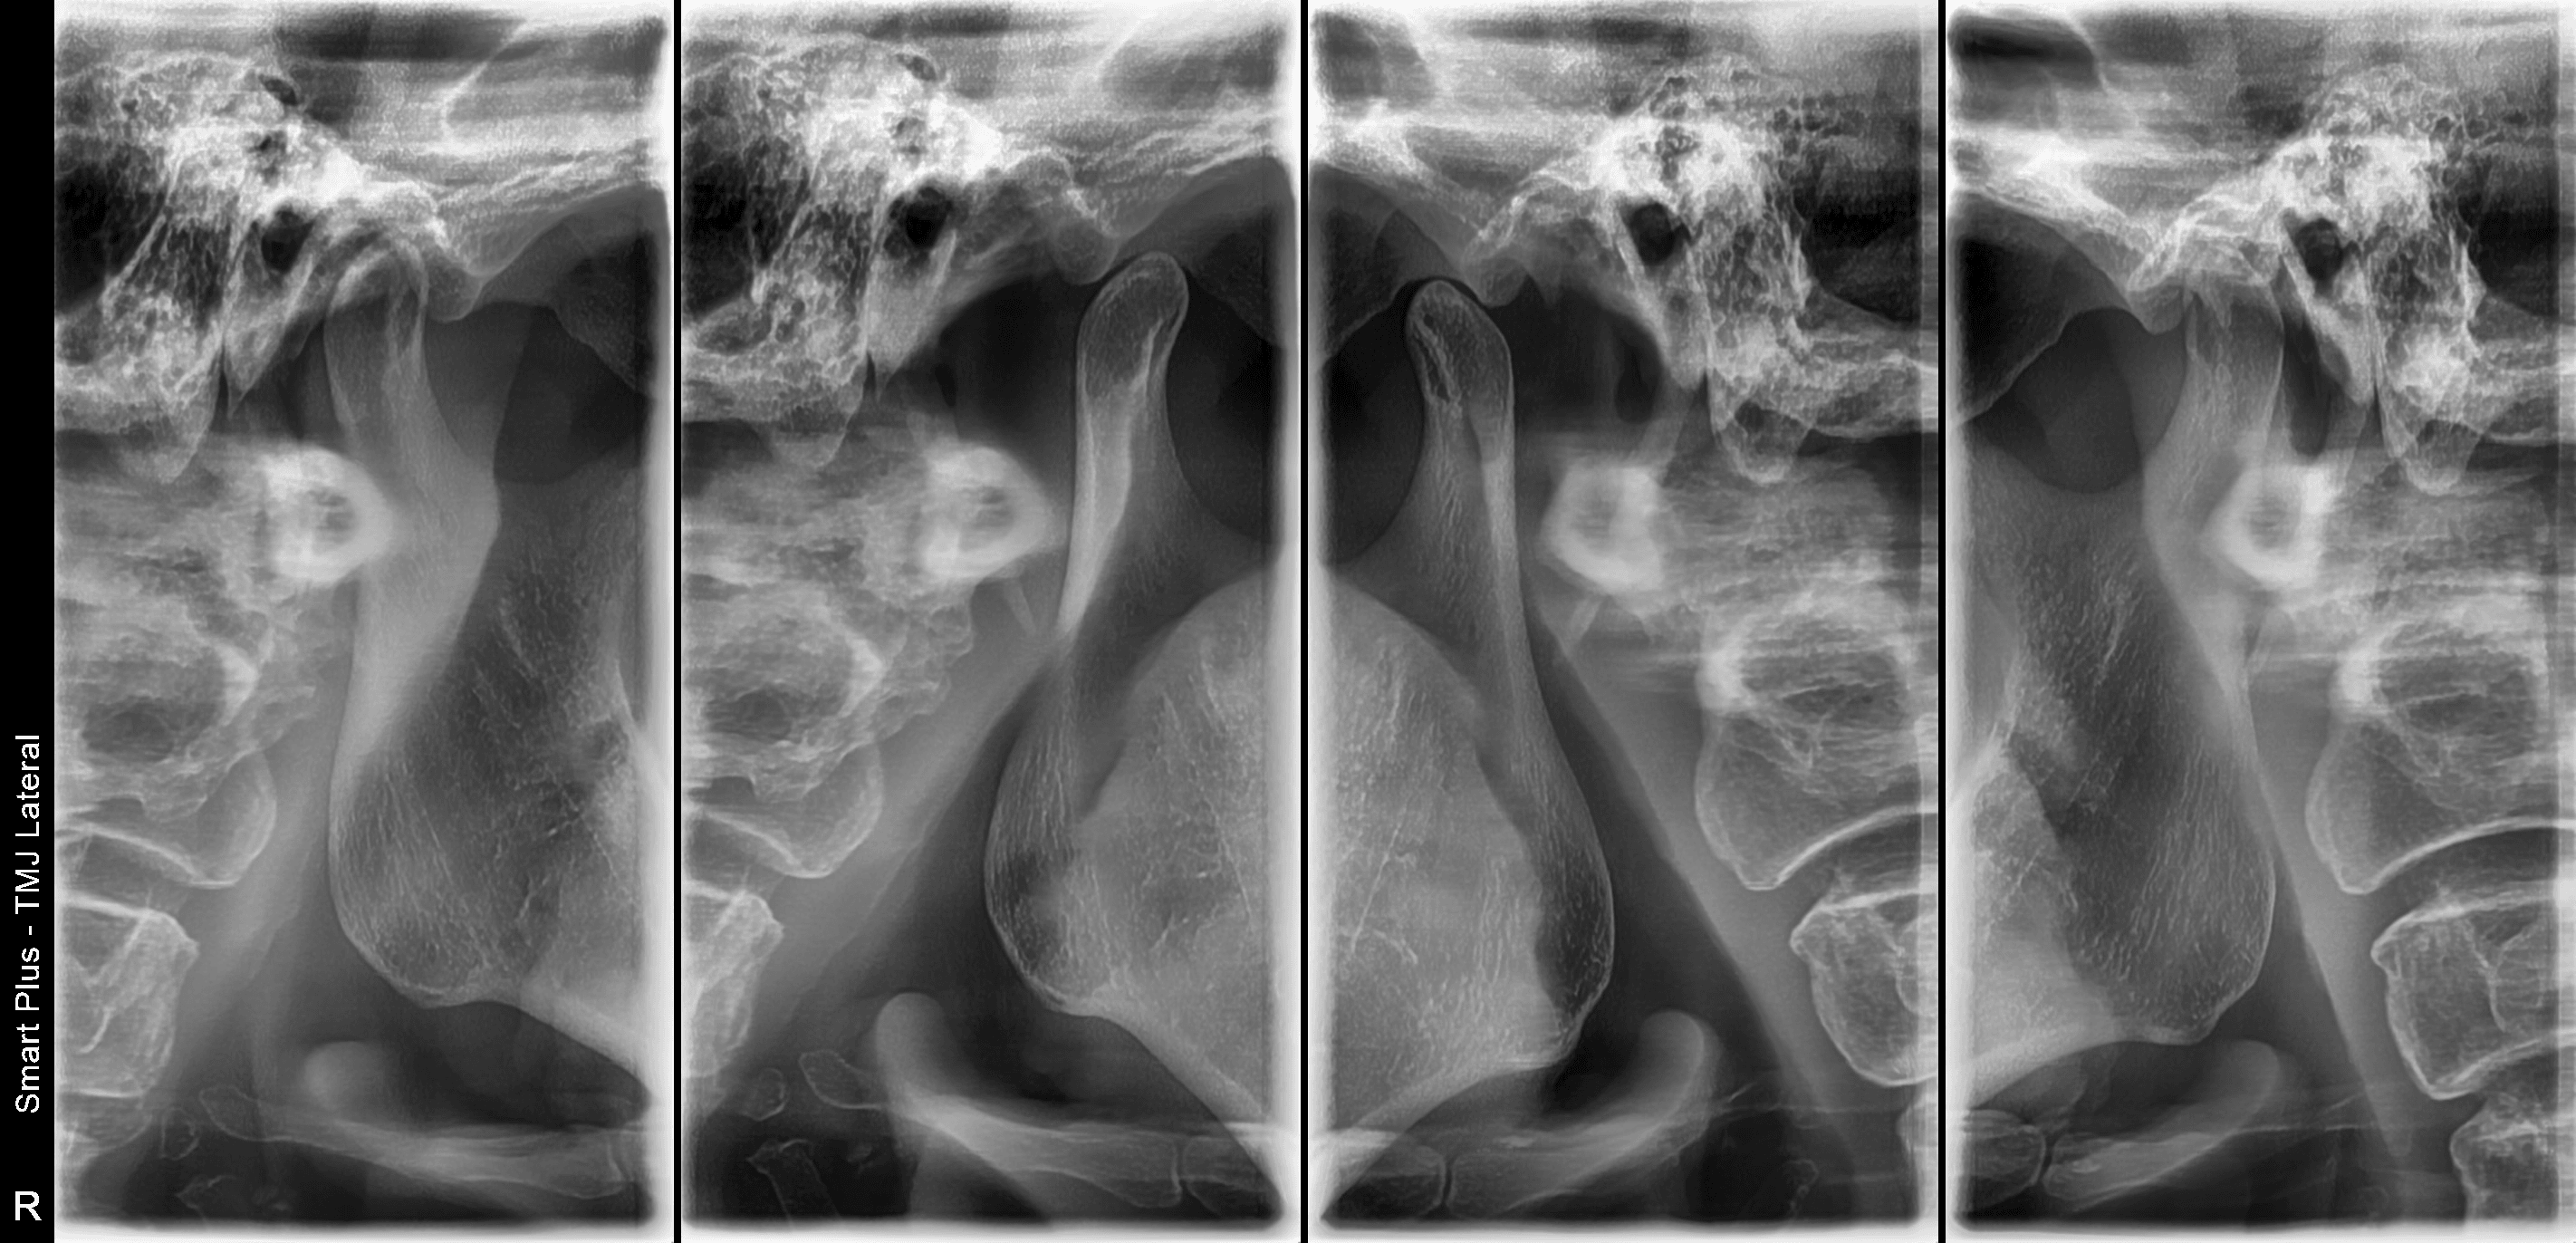

건강 상담 질문턱관절 치료 치과-3시간 전

입 벌릴 때 턱에서 소리가 나는데 병인가요? (양산 30대 후반/여 턱관절 치료 치과)

이게 턱관절 장애인가요?

턱 소리는 턱관절 디스크 이상 신호일 수 있습니다.

턱에서 딱딱 소리가 난다면 턱관절 디스크 위치 이상일 가능성이 큽니다.